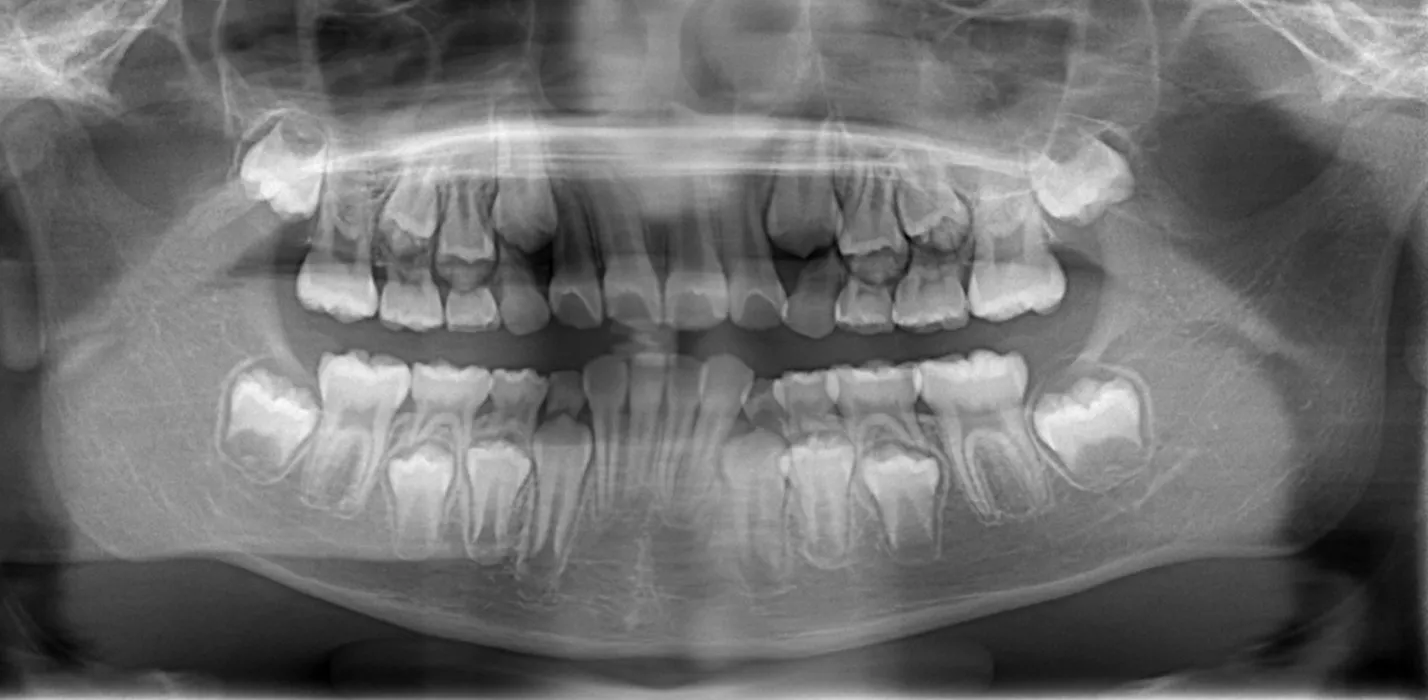

一人一人の写真・CTまたはレントゲン撮影(有料)をもとに、現在の状況を説明します。

有料カウンセリングを選択された方は、レントゲンもしくはCT撮影を行ないます。お口全体や顎の状態、骨格の様子などがよりわかりやすくなります。

お子様の場合はこれから生えてくる永久歯の状態が詳しく分かります。

大人の方の場合、CT撮影によりおくちぜんたいや顎、骨格が3D化されることでより立体的にご覧いただけます。